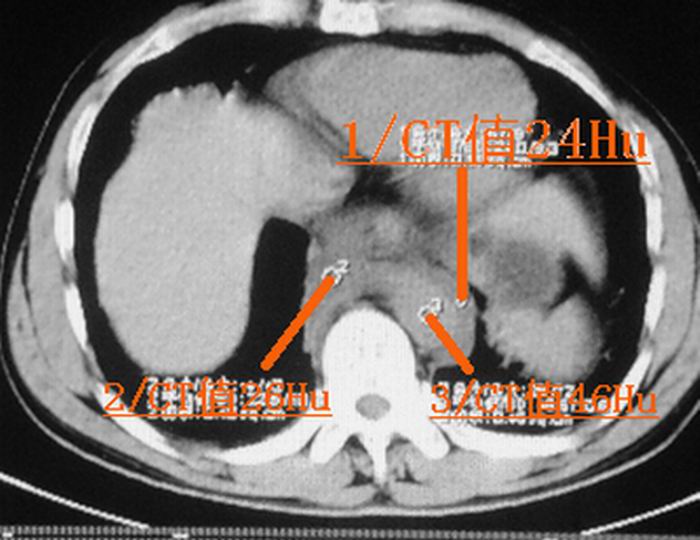

请大家看看后纵隔食道及降主动脉周围的软组织密度灶是什么?双侧膈肌脚内侧及椎管内的气体影是怎么回事?

是后纵隔出血还是出血合并有胸主动脉加层,增强扫描.

结合病史多考虑纵隔血肿形成 ,椎管及右侧腰大肌内侧气体影也与外伤有关。

要不要考虑食道中下段的损伤呢?这样血肿和气体影就都好解释了。